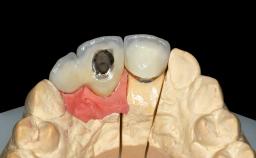

A 45-year-old woman was referred for management of an infection associated with two implant-supported crowns replacing the maxillary central incisors. Two tissue-level implants had been placed and restored with cemented single metal-ceramic crowns in those sites 4 years previously. The patient presented with a draining sinus (i.e. a pathological duct from an abscess cavity to a surface) 3 mm from the midfacial peri-implant mucosal margin of the maxillary right implant crown. She was in good general health, did not smoke, showed a good oral hygiene status, and had no history of periodontal disease. The implants were well positioned. While the patient was very satisfied with the appearance of her crowns, she had noted that the peri-implant soft tissue had receded since their insertion and was concerned about the possibility of further recession.

| Prosthesis Type | FDP |